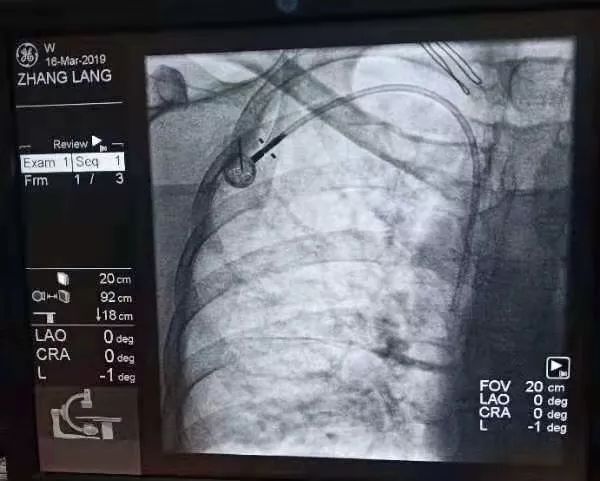

而輸液港port植入技術(shù)就可以解決這一難題。上周六,來(lái)自港閘區(qū)的張女士就在我院接受了靜脈輸液港植入術(shù)。來(lái)自上海六院的王永剛主任和瑞慈上海腫瘤中心孫英豪主任共同為患者進(jìn)行了手術(shù),輸液港完美植入患者體內(nèi),張女士術(shù)后很快就適應(yīng)了新伙伴的存在。

這項(xiàng)技術(shù)的開(kāi)展標(biāo)志著我院化療患者正式進(jìn)入“輸液港時(shí)代”,不僅能減輕患者輸液痛苦,降低藥物治療風(fēng)險(xiǎn),也大大提升了護(hù)理安全和我院靜脈輸液治療水平。